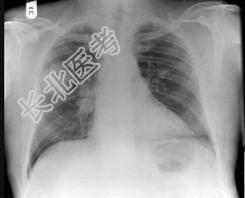

- 单项选择题58岁,男, 咳嗽、气促3个月,抽烟二十余年, 请结合胸片图选择最可能的诊断 ( )

A、肺癌

B、胸膜间皮瘤

C、肺结核

D、错构瘤

E、结节病